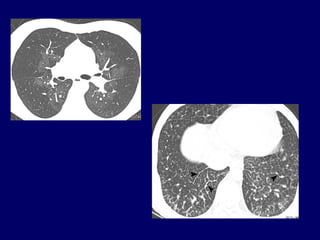

• #20 Edema dei setti interlobulari, dilatazione dei vasi linfatici spetti Aspetti clinici che la caratterizzano: ippocratismo digitale e crepitazioni bibasliare; edema interstiziale cronico dovuto all’occlsuione venulare; peggio Dlco, ipossiemia più severa. OPACITà NODULARI A VETRO SMERIGLIATO CENTROLOBULARI, IPESSIMENTO DEI SETTI INERTLOBULARI E LINFOADENOPATIE MEDIASTINICHE, MICROEMORRAGIE POLMONARI ALVEOLARI: AL BAL MCROFAGI COLMI DI EMOSIDERINA (TUTTO CIO’ NON C’Eè NELL’IPP) VENGONO INTERESSATE LE VENE PRE-SEPTALI E SEPTALI CON LESIONI FIBROTICHE OCCLUDENTI, MUSCOLAREIZZAZIONE DELLE VENULE, EDEMA, EMORRAGIE INTRALVEOLARI, DILATAZIONE LINFATICA, INFILTRATI INFIAMMATORI; COINVOLGIMENTO ANCHE DELLE ARTERIOLE DISTALI

• #21 IP pre-capillare o post-capillare? Nella malattia veno-occlusiva l’aumento della PCWP può non essere uniforme ma presente solo in alcuni lobi polmonari.